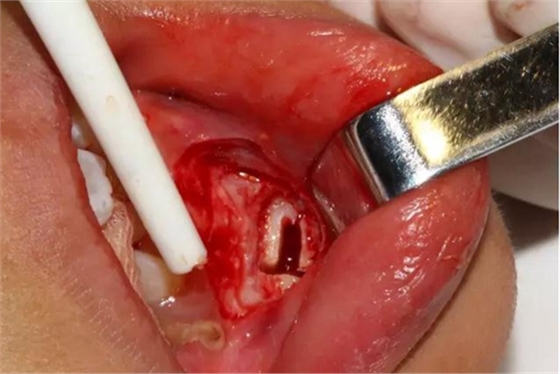

切開(kāi)、翻瓣

去除骨皮質(zhì),暴露牙冠大部分

設(shè)計(jì)冠切的位置